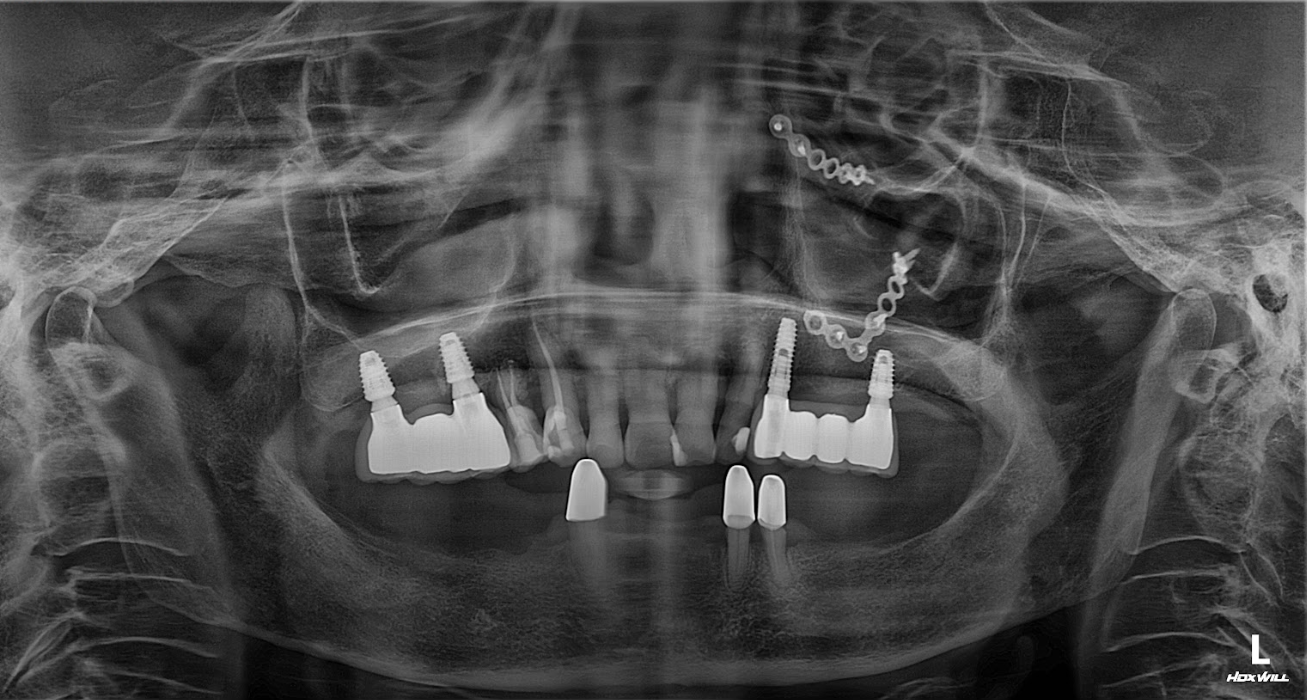

2. Lập kế hoạch điều trị kỹ thuật số

BS Bùi Văn Hưng sử dụng phần mềm Implant 3D để mô phỏng vị trí cấy ghép.

-

Lập máng hướng dẫn phẫu thuật giúp quá trình cấy ghép chính xác tuyệt đối.

3. Phẫu thuật cấy ghép Implant

ThS.BS Phạm Hùng Sơn trực tiếp thực hiện phẫu thuật.

Sử dụng hệ thống trụ Implant cao cấp, độ bền và tích hợp xương vượt trội.

4. Phục hình tạm thời

Sau khi đặt trụ, cô được gắn răng tạm để ăn nhai và giao tiếp bình thường.

5. Phục hình răng sứ hoàn thiện

Sau 3–6 tháng, khi Implant tích hợp xương, tiến hành lắp răng sứ cố định.

Kết quả: Hàm răng mới chắc khỏe, ăn nhai tự nhiên như răng thật.